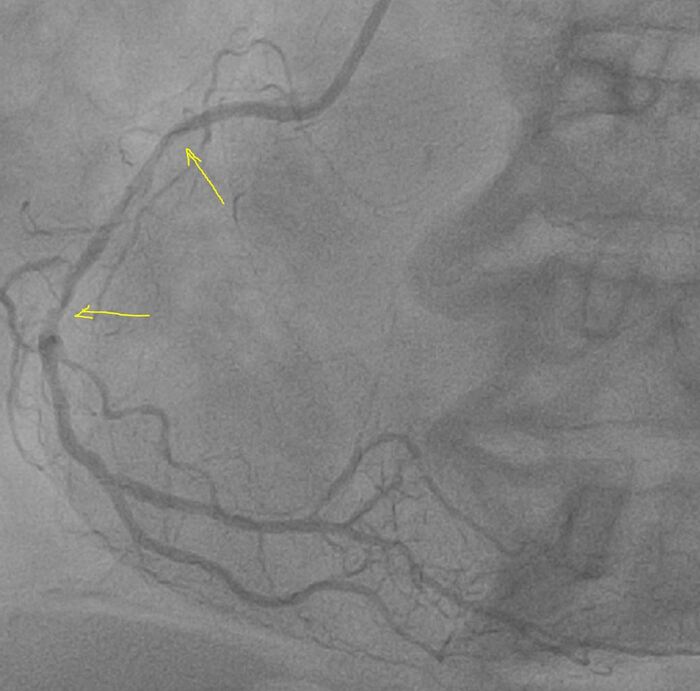

Контроль ультразвуком:

Клинически тоже все хорошо, на следующие сутки переведена в отделение. Готовится к выписке.